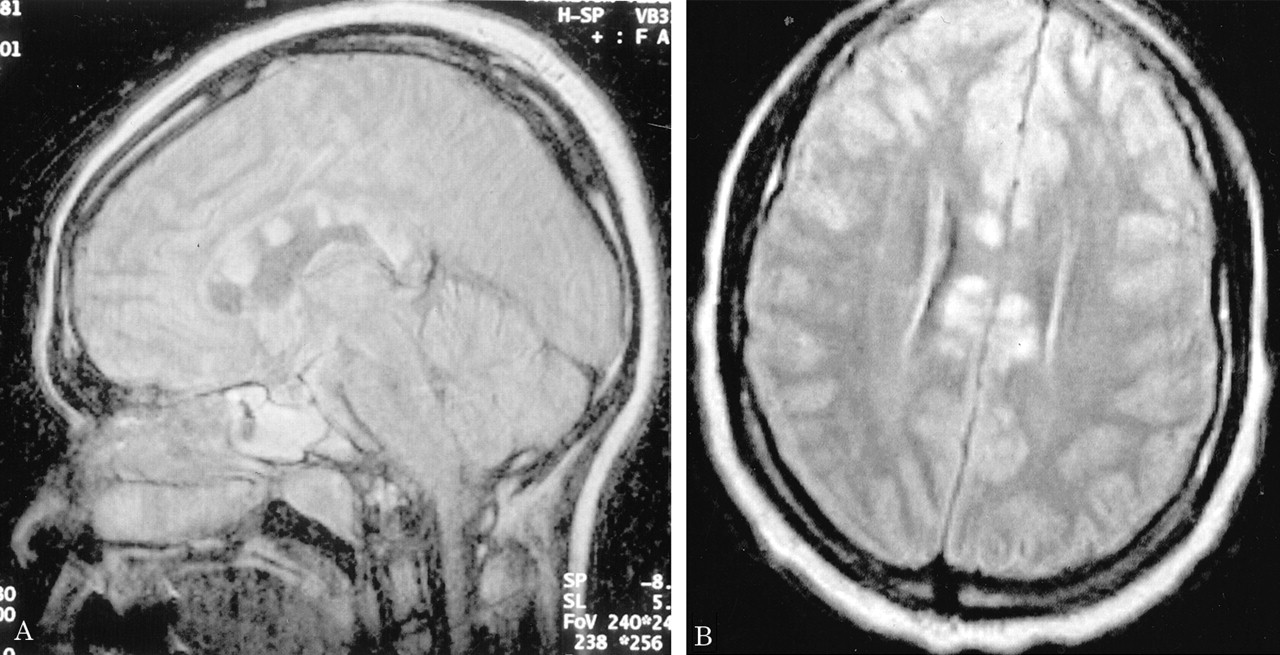

多病灶的幕上的白质病变,包括胼胝体(图1),在所有27个病人,有频繁的参与小脑,中间小脑总花梗,和脑干图1,表)。病变众多,往往是小(3 - 7毫米)但有些小病变成为支流和一些大的(> 7毫米)。19病人实质增强,当明显,导致大脑的粟粒状的外观(图2)。胼胝体的损伤通常是小的,并且涉及中央与周边的相对保留纤维;增强是变量。急性胼胝体的病变(图3)中观察到的活动脑病取而代之的是一个“充满”/穿孔先生出现在后续所有27例(图4),可能代表microinfarctions,没有出现在其他地方。胼胝体,最好在薄片(3毫米厚)矢状T1或T2矢状/质子密度加权图像,由一系列小(3毫米)中央孔相隔7毫米矢状T1和T2矢状/质子密度图像。这些扩展在整个长度的胼胝体。当急性(“雪球”)(见大图3)胼胝体的病变,慢性残余孔较大,尤其是在压部。线性缺陷有时看到的,可能反映microinfarction间接辐射在胼胝体轴突。中央孔(见图4)被认为是由于横向辐射的胼胝体轴突的微型心肌梗塞的可能性。

有深的灰色基底节和丘脑病变19病人(参见表),通常体现在T2信号强度增加,质子密度,和天赋的图像。大病变类似“巨大陷窝”43并建议纹状体外动脉增的广泛参与。三个这样的病人显示这些病变显著增强,伴随着leptomeningeal增强。实质增强(见图2)有关的大脑区域,偶尔与leptomeningeal增强(见相关表)。串行扫描被执行,增强可能是更常见。脑病减弱和病人开始恢复,只有残余病灶中央(见胼胝体的洞图4)和一些白质病变。在两个病人,增加信号强度变化在胼胝体伴随着中央胼胝体的洞在最初的MRI检查。更严重影响病人、脑和小脑萎缩随之而来。在两个这样的实例,胼胝体越来越萎缩,前面提到的胼胝体的洞几乎消失了。